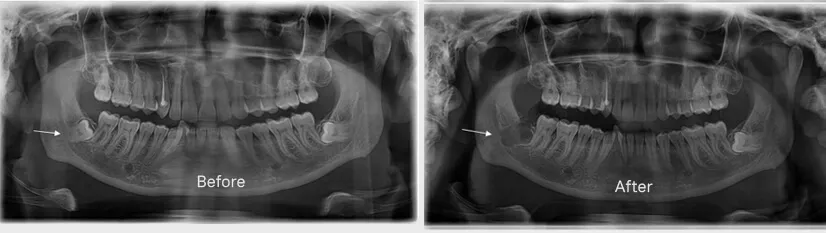

We have an in-house OPG and CT scan machine with which X-ray images are taken and a thorough examination of your mouth is done before making a treatment plan. An X-ray shows whether your teeth are impacted and if it has damaged other teeth and bone. If your teeth are impacted, our dentist is going to discuss with you the benefits and risks of surgical extraction.